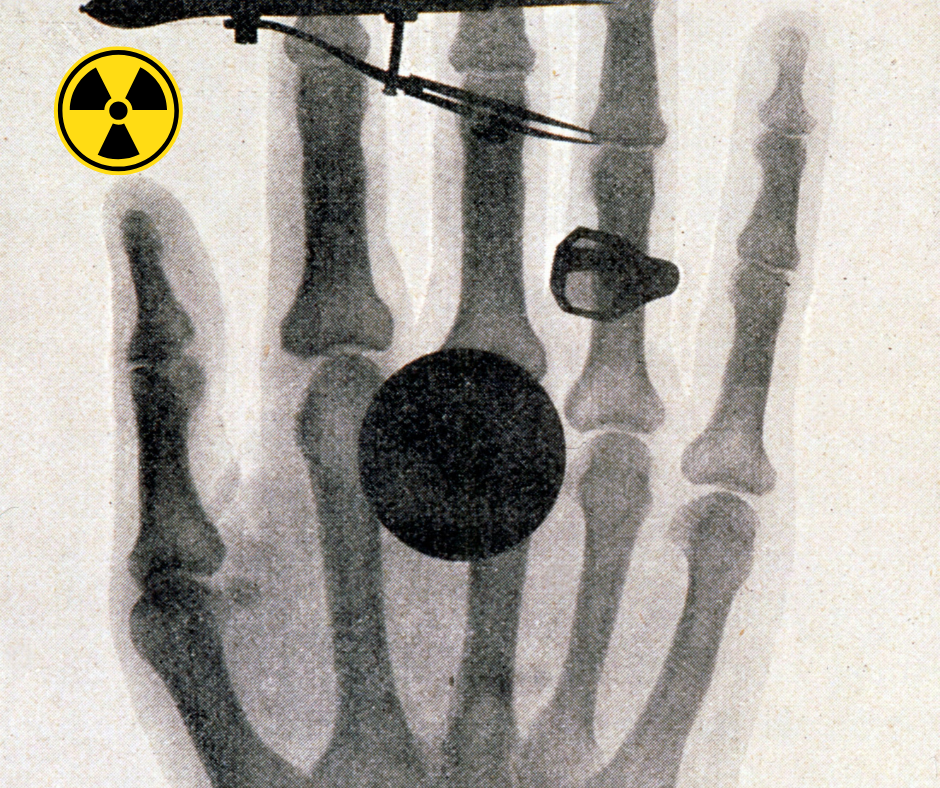

Przełomowym momentem było wykonanie pierwszego zdjęcia rentgenowskiego części ciała człowieka. W niedzielę 22 grudnia 1895 roku Röntgen poprosił swoją żonę Berthę do laboratorium, gdzie położył jej lewą dłoń (z pierścionkiem na palcu) na kasecie z płytą fotograficzną. Po 15-minutowej ekspozycji powstało historyczne zdjęcie, ukazujące kości dłoni oraz zarys obrączki. Niedługo potem, 28 grudnia 1895 roku, opublikował wyniki swoich badań w czasopiśmie Würzburgskiego Towarzystwa Fizyczno-Medycznego, oficjalnie ogłaszając światu swoje odkrycie.